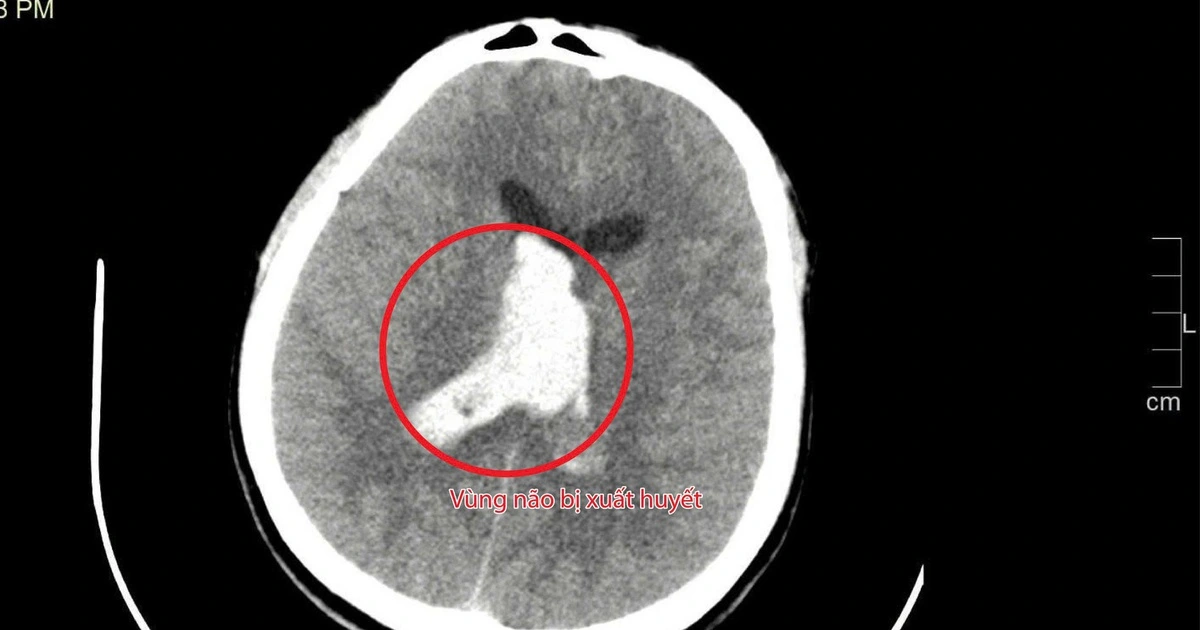

Xuất hiện những cơn đau đầu nhẹ, một giáo viên 28 tuổi ở Cà Mau cứ tưởng do áp lực công việc, sau đó bị đột quỵ nguy kịch.